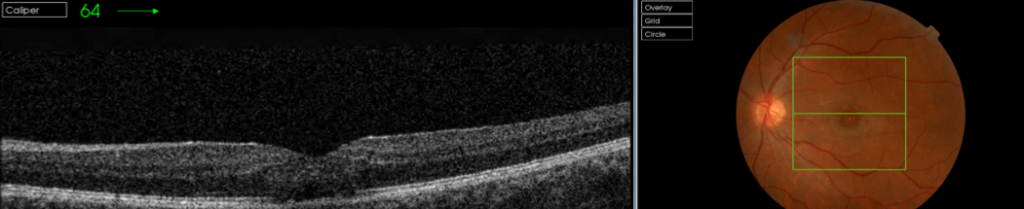

Actualmente podemos caracterizar las lesiones mediante las pruebas de imagen que aportan valoración cuantitativa y cualitativa. Es interesante, adicionalmente a la exploración funduscópica estudiar las lesiones mediante retinografía, OCT, angio-OCT, autofluorescencia, microperimetría y oftalmoscopía láser confocal(SLO). Todas ellas aportan información complementaria en el estudio, diagnóstico y seguimiento de las lesiones. A continuación se muestran retinografías y OCTs de un caso de retinopatía solar y un agujero macular producido por la acción de un láser en una discoteca ( Figuras 1,2,3,4)

La tomografía de coherencia óptica (OCT

) muestra un espacio hiporreflectivo característico en la retina externa en pacientes con retinopatía solar crónica. Los hallazgos son congruentes con la histopatología de esta condición y constituyen una herramienta clínica útil para confirmar el diagnóstico. 8,11

Figuras 1 y 2. Retinopatía solar bilateral crónica en paciente varón, ocurrida en el año 1970 mirando un eclipse solar, en el momento de la lesión el paciente tenía 38 años, agudeza OD:07 NMA, agudeza OI: 0.5, NMAE ( no mejora con agujero estenopeico).